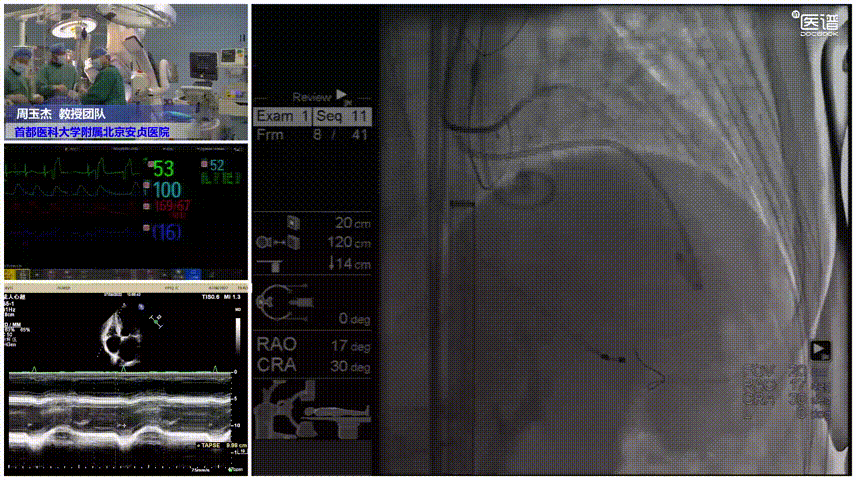

近日,在首都医科大学附属北京安贞医院纪智礼书记和张宏家院长的大力支持下,周玉杰副院长、老年心血管病中心史冬梅主任、王志坚主任、郭永和主任带领TAVR团队,在手术室、麻醉科、超声科、影像科等科室的全力配合下,成功应用TriGUARD3™抗栓塞远端脑保护装置为一名高龄低体重、严重二叶瓣畸形、重度主动脉瓣狭窄的冠脉高风险、脑梗高风险患者完成经导管主动脉瓣置换术(TAVR),术后患者恢复状况良好。这也是全球首例冠脉保护与TriGUARD3™抗栓塞远端脑保护装置同时辅助TAVR手术实施的病例。

手术过程

脑保护

患者既往有COPD病史,且体重极低,为避免麻醉相关并发症,麻醉方式上选择局部麻醉。在左侧股动脉上下两个穿刺点行股动脉穿刺,上穿刺点置入6F鞘管,下穿刺点置入8F鞘管。右侧股动脉切开处送入20F大鞘。沿左股动脉8F鞘,交换送入TriGUARD3™脑保护装置,透视下顺利过弓,准确定位后成功释放过滤器,全部覆盖主动脉弓的三条血管。经TriGUARD3™送入5F猪尾至升主动脉。

脑保护释放

冠脉保护

沿左股动脉6F鞘,将JL4.0指引导管送至LM开口,送 SION 导丝至前降支远端,循SION导丝依次送Guidezilla II 延长导管和Sprinter 2.5*12m球囊至左冠内进行冠脉保护。

冠脉保护完成